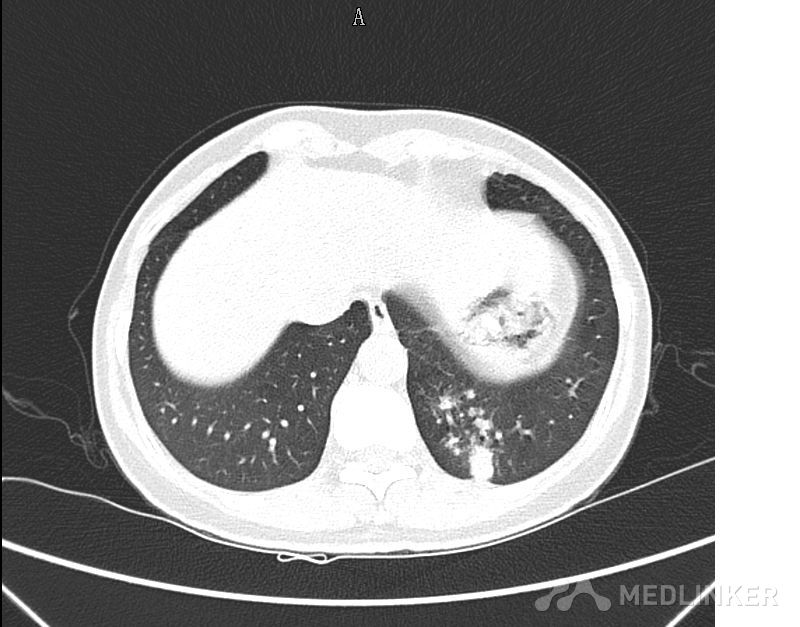

大家看看这个肺部的占位可能是什么?

肺部肿物

以CT图片为准,中年男性,反复咳嗽半个月入院,有低热,痰不多,无咯血,饮食睡眠正常。